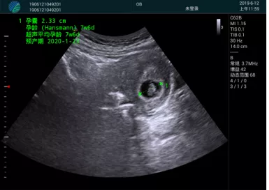

病例一:

清晰顯示孕囊,通過軟件包計算孕齡7w+6d

M20實時引導,術(shù)中清晰顯示孕囊被破壞和抽吸針的過程,清晰顯示吸引針

抽吸結(jié)束后縱切子宮,孕囊已被完全抽吸,未見明顯殘留

橫切子宮,發(fā)現(xiàn)右側(cè)宮腔靠近宮角處有少許脫模樣殘留

M20引導下,抽吸針找到右側(cè)宮角處再次清掃

二次抽吸后再次進行超聲檢查,宮腔未見殘留,宮腔線清晰顯示